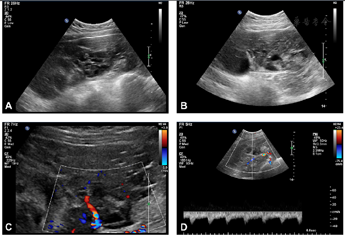

患儿10岁时因下腹持续性坠痛就诊,经腹超声检查显示腹盆腔内巨大低回声,范围约23.0 cm×16.4 cm×7.2 cm,边界清,内可见多处散在小无回声区,部分区域呈蜂窝状(实性区域>80%),CDFI:内部及周边可见中度丰富的动静脉血流(图1)。左卵巢未显示,右卵巢大小约2.6 cm×2.9 cm,形态结构未见异常,子宫大小形态未见异常。考虑左附件来源实性包块。盆腔常规+增强MRI:盆腔实性为主肿物,增强扫描见显著强化。实验室检查:孕酮>40.00 ng/ml↑(0.38~2.28 ng/ml),雌二醇514.00 pg/ml↑(27~122 pg/ml),血LDH 335 U/L↑(0~300 U/L),神经元特异性烯醇化酶(NSE) 26.8 ng/ml↑(0~16.3 ng/ml)。

术后2年经腹超声发现右卵巢无回声区,大小4.8 cm×3.5 cm×3.5 cm,形态规则,边界清,内透声好。患儿雌孕激素水平正常,考虑不能排除生理性囊肿,随访观察半年,右附件区囊性包块逐渐增大至21.3 cm×18.1 cm×9.9 cm,形态规则,边界清,内透声好,其周边可见多发小卵泡样无回声结构,直径约0.5~1 cm(图2),CDFI:包块内未见明确血流信号。CT示腹盆腔内巨大囊性占位病变,增强扫描无强化。实验室检查:雌二醇171 pg/ml↑(27~122 pg/ml),孕酮、血LDH、NSE均正常。